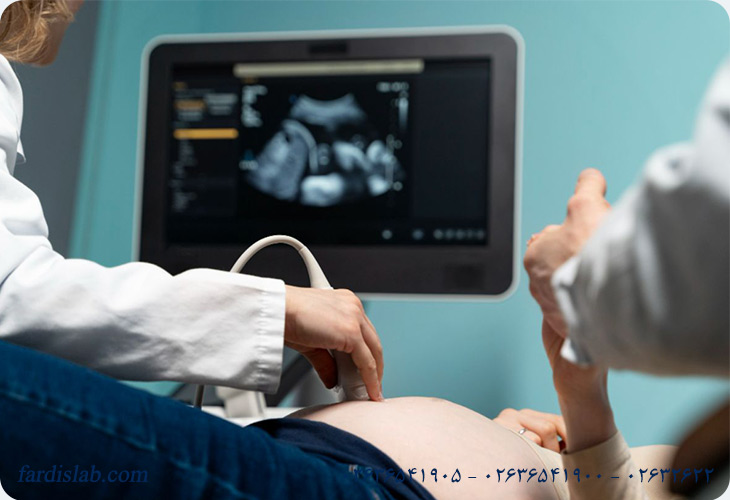

2. سونوگرافی NT و NB

در کنار آزمایش خون، سونوگرافی دقیق جنین انجام میشود تا برخی معیارهای کلیدی اندازهگیری شوند: مهمترین آنها شفافیت پشت گردن جنین Nuchal Translucency یا NT است، که مقدار مایع زیر پوست پشت گردن را نشان میدهد و در مواردی که ریسک اختلالات کروموزومی بیشتر است، این مقدار ممکن است افزایش یابد. همچنین بررسی وجود استخوان بینی Nasal Bone یا NB در سونوگرافی میتواند به افزایش دقت ارزیابی ریسک کمک کند، چون در بسیاری از جنینهای مبتلا به سندروم داون، استخوان بینی در این دوره زودتر از حد طبیعی تشکیل نمیشود.

3. سونوگرافی NT و NB

سونوگرافی دقیق برای اندازهگیری ضخامت پشت گردن جنین(NT) و بررسی استخوان بینی(NB) انجام میشود. تکنیک دقیق و مهارت اپراتور برای دقت نتایج حیاتی است.